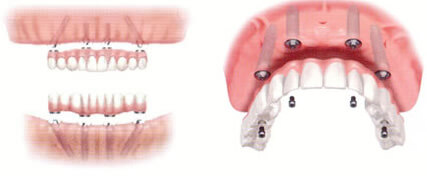

下顎は4本、上顎は4~6本のインプラントでフルブリッジを固定し、手術即日に噛む機能と審美性を回復するまったく新しいコンセプトの術式です。従来、歯を全て失ってしまった方のインプラント治療には、上下それぞれ8~10本のインプラントを必要としてきました。又、治療期間は非常に長く、治療費もとても高額でした。オールオン4なら治療コストを低減でき、治療期間も大幅に短縮する事が可能です。

オールオン4の症例の多さは、当クリニックのインプラント治療の特徴でもあります。「オールオン4」とは、歯が1本も残っていない(無歯顎)場合や、残っている歯が数本である場合に、片顎4本~6本のインプラントを埋入し全ての歯を支えるという術式です。これまでは、歯が1本も残っていない場合は総入れ歯か、数多くのインプラントを埋入するという治療法でした。総入れ歯を長期に渡り使用してきた方は骨も吸収し、インプラントをするには骨造成等の手術が必要になるケースも多くある為、従来の治療法は、患者様の経済的負担も大きく、治療期間も大変長いものでした。

「オールオン4」という治療法は、一般的に手術と同時に仮歯を装着する為、審美的な回復が即日可能であると共に、ほとんどのケースにおいて、骨造成等の必要がありません。オーキッド歯科クリニックの術式は上顎の場合、ほぼ100%フラップレス方式(歯茎を切開しない)を用いる為、術後の腫れや痛みも最低限に抑えることが可能です。また、治療期間もわずか一日で仮歯が入りますので、簡単なお食事から始める事が出来ます。オーキッド歯科クリニックのオールオン4は、多くの症例を積んできた過程の中で術式そのものをよりシンプルに改良してきた為、さらに手術時間の短縮が可能となり患者様の心身的負担も軽減することが出来ました。多くの患者様がこの「オールオン4」により笑顔を取り戻しています。